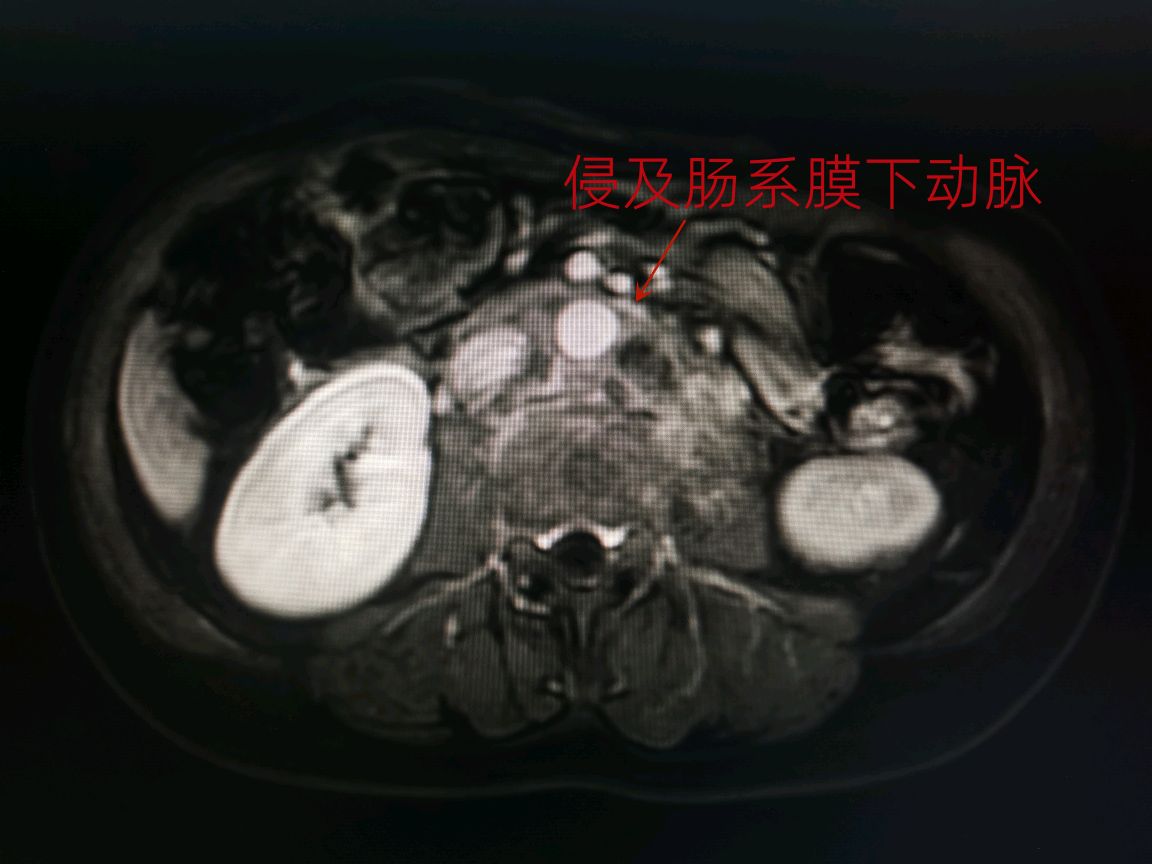

柯女士是一位45岁的中年女性,有着姣好的面容、高挑的身材和开朗的性格。2022年5月,她突然感到左侧腰背部持续疼痛,无法进食,经过一系列检查后被诊断为左侧肾盂癌伴腹膜后巨大淋巴结转移,侵及周围肌肉和腰椎,侵及左肾动脉并包绕大部分主动脉。这样在左侧腹部形成一个直径近10cm,长度超过15cm的与血管、腰肌、椎体相融合的固定不动的巨大肿瘤。

经过充分的术前准备,我们于2022年6月14日为患者进行了手术治疗,术中切除了左侧肾脏、肾上腺、主动脉周围淋巴结、肿瘤侵犯的肌肉和部分腰椎横突;肿瘤侵及的部分主动脉,也进行了部分切除和修补(注:主动脉是人体最大动脉,一般只有心脏和大血管外科医生能进行修补),并在腰椎侵犯处放钛夹标注将来放疗部位。